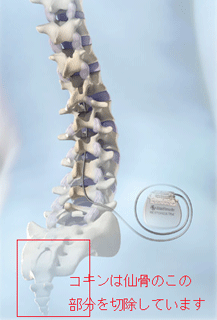

昨晩積もった雪道を安全運転で出発です今日、医大病院ペインセンターの予約は11時です。積雪は15センチぐらいで、冬タイヤは12月に新品に交換していたので安心感はあるのだが、シーズン最初の雪上運転で慎重ですコキン(母さん)が9年前、仙骨脊索腫で12時間がかりで、腹部からと背部と前後アプローチの仙骨の大部分を切除したのですが、手術時からコキンに携わり診て戴いた先生が今もペインセンターで、疼痛緩和にあたってくださり、コキンが信頼第一のドクターの診察日です。画像は医大のパンフから

11月の入院は、かあさんに大きな効果がありました。腰部神経根と腹部内蔵神経にブロックを施術して戴いたのです。先生方の今年春以来の懸命な、ご尽力により場所というか、かあさんのお腹の中を熟知してくださった故でしょうか、腰部ではビリッときたようです。それよりも担当の先生から「2月の本当に難しい仙骨摘出をして、これから先ズッと病院生活にならへんやろか。退院できるんやろか」と心配していたんですよ」と聞かされ、又「今の状況は素晴らしい、精神的にも身体的にも回復ですよ」のお話で、「痛みは一緒や、ちっともようなってない」とばかり思い考えていたかあさんが、どうやら変わって退院してきました。 金沢大学医学部整形学科のウェブサイトから、こんな記述と写真を見つけました。この手術もまた金沢大学整形外科で考案した手術方法です。仙骨にできた腫瘍を一塊として摘出する手術方法です。仙骨にできた悪性腫瘍(脊索腫、骨巨細胞腫、転移性腫瘍など)が適応になります。仙骨は脊椎の一番下に存在し、骨盤をつないでおり、脊椎の礎となるところです。そのため仙骨摘出後の再建が大きな問題となりますが、これに関しても金沢大学工学部と共同で研究を重ねて独自の再建法を考案しました。 かあさんは、何とか歩ける機能は温存しておきたいという一念から仙骨の上部は残して、脊索腫が認められる、上縁で切除をしたんだから、大きな神経を切り大切な排泄機能をなくしてでも、歩きたいと考えたのだから、これからも生きている限り痛みと妥協して、好きな時に好きなことをして、痛みを忘れる時間を作りながら、頑張っていこうよ。周囲の里のすべての人たちが、かあさんが、笑顔と大きな声でみんなの輪のなかへ戻ってくる日を待っていてくれるんだから。 もう一つの変化は複合病棟だったので、同室に上顎ガンで手術後、放射線治療中の60歳台の女性と、40歳台の舌ガンの女性から「ガンと闘う強さと明るさ」のパワーをもらって退院してきたのです。家の東西南北、こんな紅葉に包まれた日に、ニッコリ笑って元気になって退院です。そして、昨年11月27日に細胞診の為、2回目の背中の手術をしてから1年グラウンドゴルフを1ラウンド仲間の皆さんの励ましといたわりの中でゲームに参加しました。スコアは21、まだまだ力はありました。カラオケの新曲にも挑んでいます。痛みは無くなりはしませんが、忘れる時間が少しでも長くなれば、奇跡がおこるんではとやがて山里には、厳しい冬が訪れます。訪問看護師さんと笑いながら、話をする声が聞こえます。里の冬は寒さが厳しいのですが、この里には人の温もりがいつもあります。